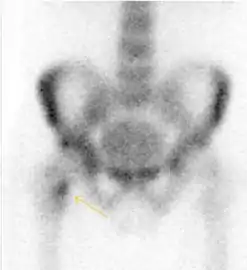

Nuclear Medicine

Bone scanning in people with hip pain can be complementary to other imaging studies, mainly in indeterminate bone lesions to clarify whether it is an active lesion with abnormal radiotracer accumulation. Nevertheless, MRI has replaced scintigraphy in the diagnosis of most of these conditions. An example is stress or insufficiency fractures: increased uptake is usually present in around 80% of fractures within 24 h, and 95% of fractures reveal activity by 72 h following trauma, showing an overall sensitivity of 93% and specificity of 95%. MRI is superior to bone scans in terms of sensitivity (99%-100%) and specificity (100%). Moreover, a bone scan does not provide detailed anatomical location of the fracture, and further imaging is usually required.[1]

Figure 10:

Stress femoral neck fracture in a young athlete barely visible in X-ray film as a sclerotic line (arrow)[1]

In this case, Tc 99 scintigraphy shows a band of uptake[1]

Furthermore, T1 (left) and DP fat saturated (right) weighted MR images showed the fracture line and a pattern of edema.[1]